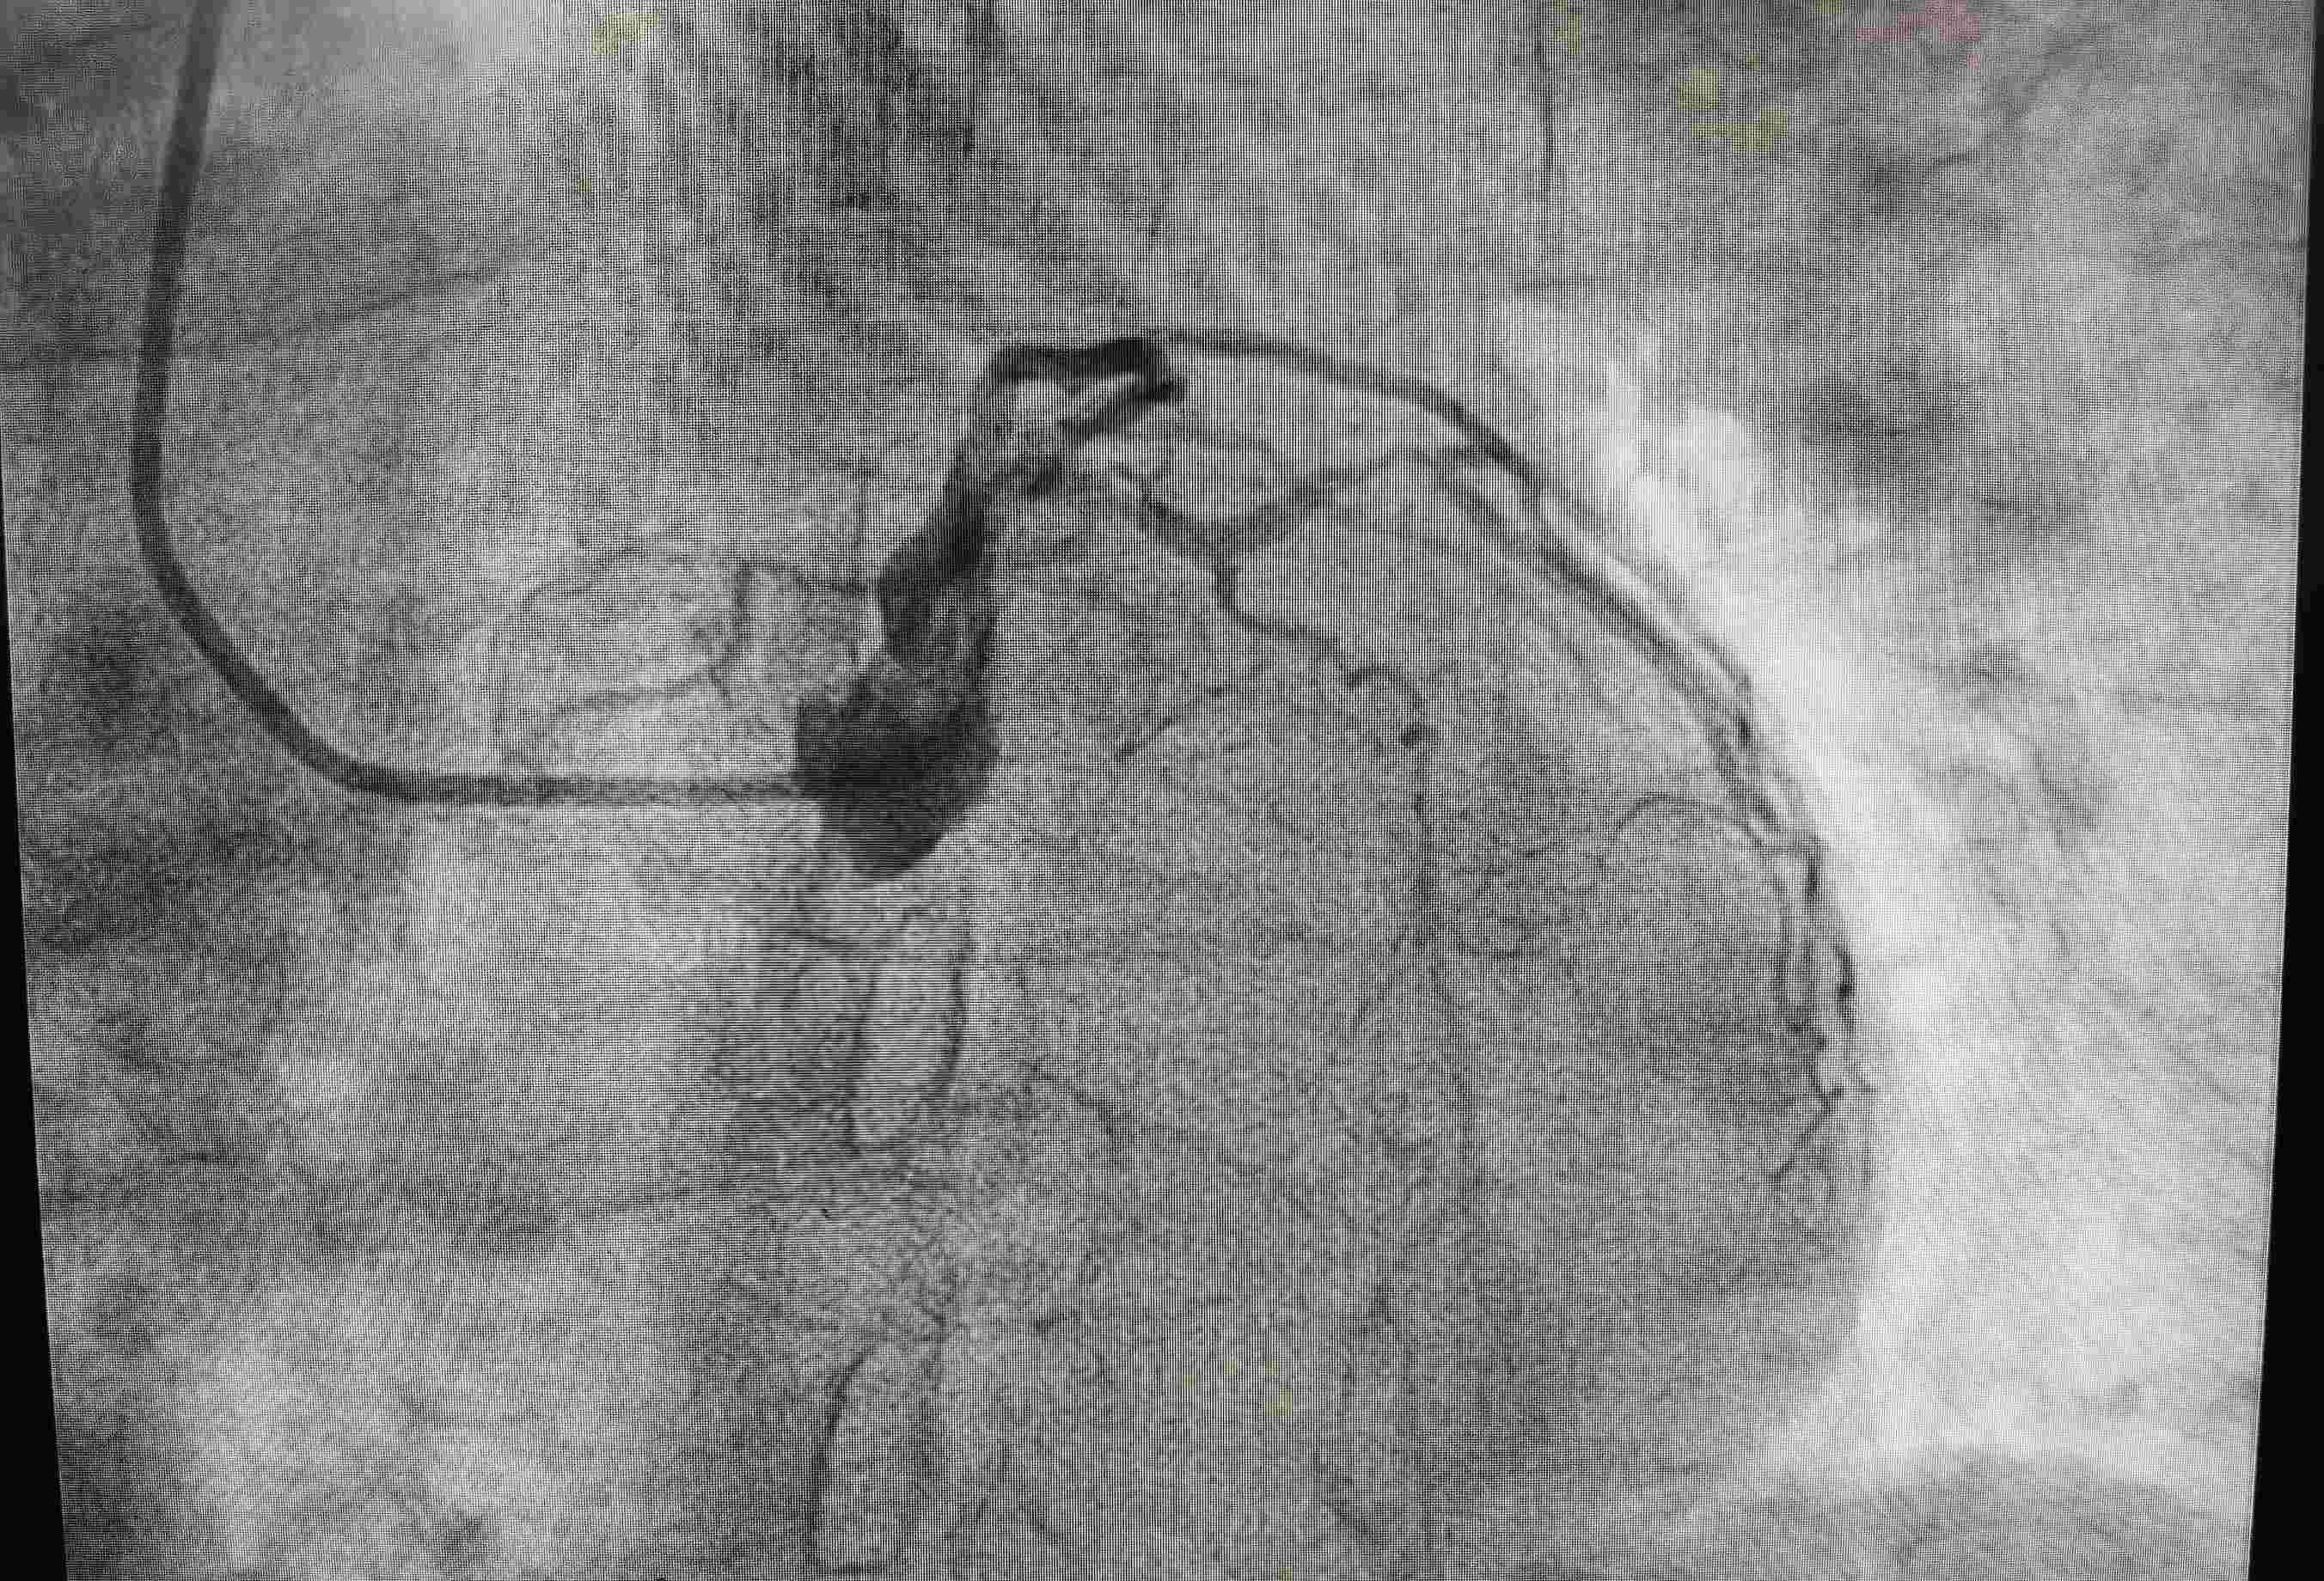

术后血管堵塞造影图片

转诊后,卫生院及时向柳州市人民医院胸痛中心追踪病人的治疗情况,经了解,该患者左前降支近中端次全闭塞、左前降支远端血流TIMI2级、旋支中端狭窄85%、右冠脉近段狭窄60%,置入支架1枚,经过及时救治、患者已转危为安!